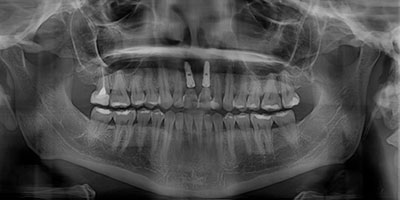

Rx Panoramica Post Quirúrgica

Posteriormente con citas de revisión periódicas damos tiempo de integración de 6 meses y procedemos a rehabilitar el caso con coronas de cerámica.